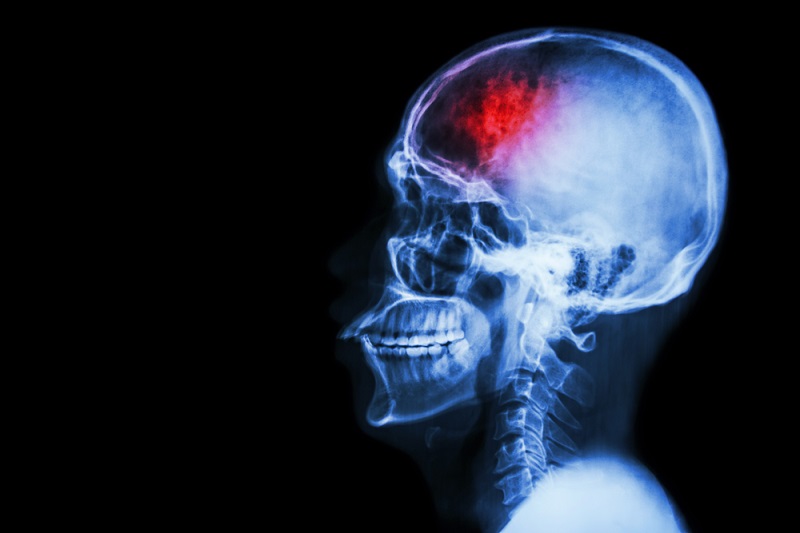

Todos sabemos lo peligroso que puede llegar a ser un derrame cerebral (también conocido como apoplejía o ictus), y qué implicaciones tiene para la salud. La capacidad de reconocer sus signos oportunamente, no solo podría salvar tu vida, sino también evitarte el terrible sufrimiento de una consecuente discapacidad. ¿Sabías que, si se proporciona asistencia médica entre 3-5 horas después de la aparición de los primeros síntomas, los efectos adversos podrían minimizarse considerablemente?

La apoplejía es un accidente cerebrovascular, caracterizado por la ruptura repentina de un vaso sanguíneo del cerebro, generalmente causada por un brusco pico de presión arterial. Años atrás, el derrame cerebral era un problema común en las personas mayores de 60 años, sin embargo, en la actualidad, son cada vez más los jóvenes que se ven afectados por este peligroso y potencialmente mortal trastorno.